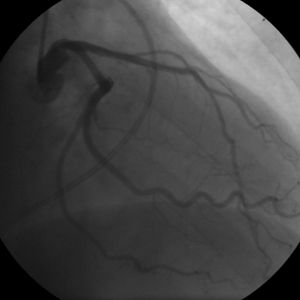

관상동맥질환의 진단에는 여러 방법이 사용된다. 안정시 심전도는 약 70%에서 정상 소견을 보이지만, 운동 심전도(스트레스 검사)는 단계적인 운동 부하량에 따라 허혈성 소견을 관찰할 수 있어 진단에 가장 널리 사용되는 방법이다. 방사성 동위원소 검사를 통해 박출계수(ejection fraction)나 심근 관류를 측정할 수 있다.

박출계수는 정상에서 운동 시 증가하지만 관상동맥질환에서는 감소한다. 관상동맥조영술(coronary arteriography)은 관상동맥 협착의 위치와 정도를 파악하는 데 가장 중요한 검사이며, 심실 조영술로 심실 기능과 박출계수를 측정할 수 있다. 동맥 조영술 상 관상동맥 직경이 50% 이상 감소하면(단면적의 75% 이상) 유의미한 협착, 70% 이상 감소하면(단면적의 90% 감소) 심한 협착으로 간주한다.[28]

안정적인 증상이 있는 환자의 경우, 컴퓨터 단층 혈관 조영술(CTA), PET, SPECT/핵 스트레스 검사/심근 신티그래피, 스트레스 심초음파 검사 등의 비침습적 영상 검사를 통해 CAD를 진단할 수 있다. 운동부하 심전도 검사는 위양성 및 위음성 결과 위험으로 인해 비침습적 영상 검사보다 덜 선호된다. 증상이 없고 CAD 발생 위험이 낮은 사람에게는 비침습적 영상 검사가 권장되지 않는다.[73][74] 비침습적 검사가 결정적이지 않거나 고위험군인 경우 관상동맥 조영술(ICA)을 이용한 침습적 검사를 시행할 수 있다.[72]